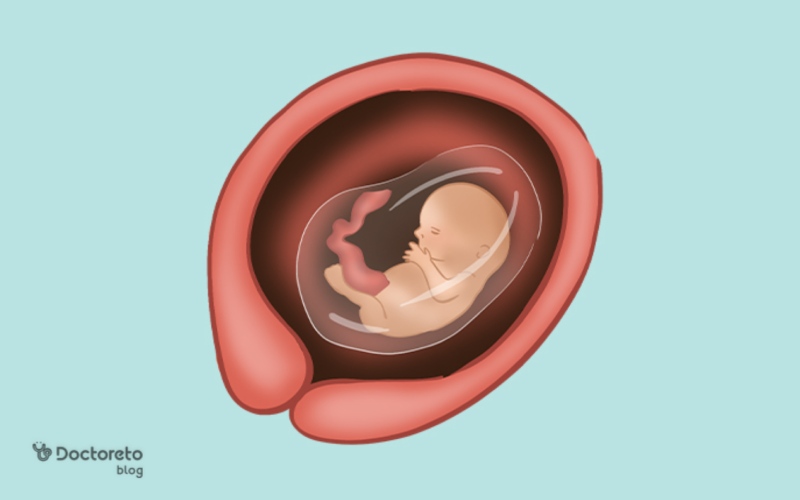

در هفته سیزدهم بارداری بیشتر اندامهای جنین تشکیل و بیشتر از قبل شبیه به نوزاد انسان شده است اما هنوز در حال تکامل است. برخی علائم اولیه بارداری کاهش پیدا میکنند و علائم جدیدی ظاهر میشوند. در این زمان جنین شروع به حرکتهای نرم در رحم میکند هرچند مادر هنوز آنها را احساس نمیکند. همچنین صورت جنین واضحتر میشود و اندامهای او، به خصوص استخوانها و اندامهای تناسلی، در حال تکامل هستند. اگر در هفته ۱۳ بارداری هستید یا بهزودی وارد این مرحله از بارداری میشوید، در این مطلب از دکترتو همراه ما باشید. در ادامه رشد جنین و تغییرات بدن مادر در این هفته را توضیح میدهیم.

جنین در هفته سیزدهم بارداری تقریبا ۷ تا ۸ سانتیمتر است. میتواند در رحم حرکت کند و حتی انگشت خود را بمکد. در این هفته تغییرات زیر ایجاد میشود:

در هفته سیزدهم، جنین شبیه یک نوزاد کوچک است، با سر بزرگتر از بدن. استخوانها سخت میشوند، انگشتان کامل تشکیل شده و میتواند شست بمکد. رودهها به شکم منتقل شده و کلیهها کار میکنند. پوست نازک و شفاف است و موهای کرکی (لانوگو) ظاهر میشود. اندازهاش حدود ۷ تا ۸ سانتیمتر از سر تا باسن و وزن ۲۰ تا ۳۰ گرم است. این مرحله گذار به سهماهه دوم است با رشد سریع ارگانها.

اندازه جنین در هفته سیزدهم حدود ۷ تا ۸ سانتیمتر از سر تا باسن (CRL) و وزن حدود ۱۴ تا ۲۱ گرم است و شبیه یک لیمو است. رشد سریع است و ارگانها کامل میشوند. رژیم غذایی مادر روی رشد جنین تأثیر دارد.

در هفته سیزدهم بارداری تمامی اندامهای جنین تشکیل شده است. جنین بیشتر از قبل به انسان شباهت دارد و اندامهای جنسی رشد کردهاند. جنین در این هفته میتواند حرکت کند، مایعات را قورت دهد و ادرار کند. موهای ظریفی روی بدن او رشد کردهاند. اندازه جنین حدود ۷ تا ۸ سانتیمتر و تقریبا اندازه یک هلو است.